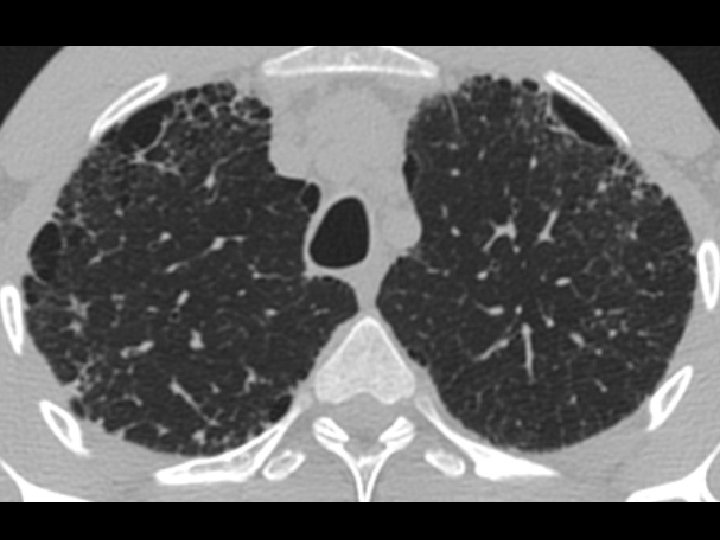

High-resolution CT scan

Subpleural, basal predominance Reticular abnormality Honeycombing with traction bronchiectasis UIPUIP Pattern

Subpleural, basal predominance Reticular abnormality Honeycombing with traction bronchiectasis Profuse micronodules UIPUIP Pattern Inconsistent with UIP Pattern